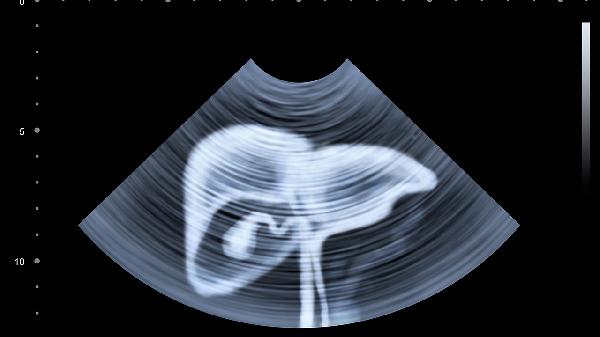

每3-6个月要做肝功能、病毒DNA检测,每年至少1次肝脏超声+甲胎蛋白检查,相当于给肝脏做"年度安全评估"。